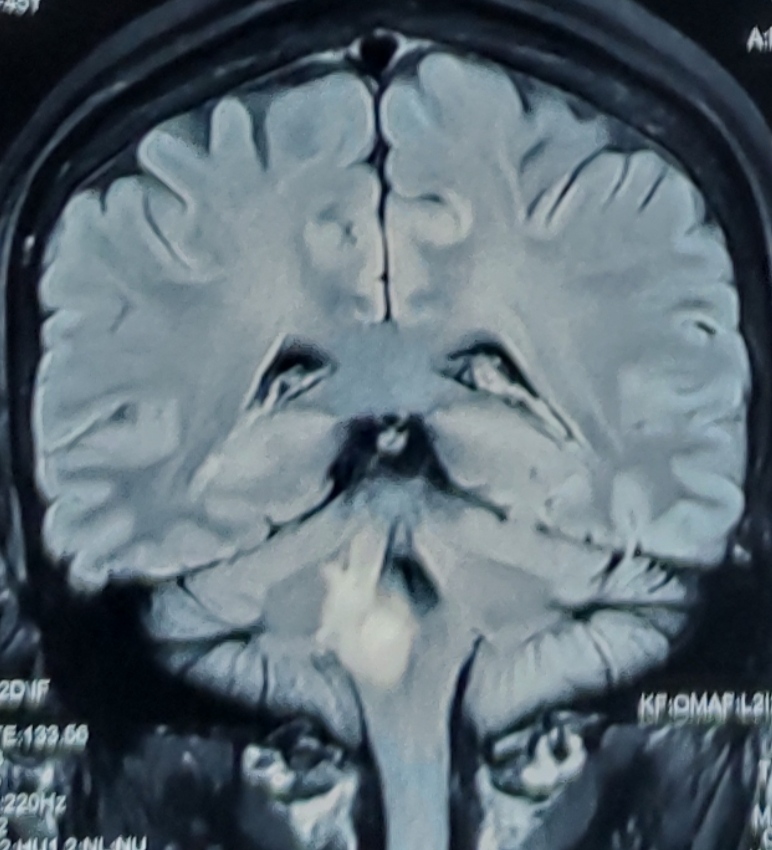

患者女,45岁,因头晕视物模糊伴左侧肢体肌力乏力一月入院。核磁共振报告延髓右侧-桥小脑臂病变,考虑肿瘤可能性大,炎性病变待删。患者及家属强烈要求活检明确病情,科室讨论决定采用立体定向技术活检,因为延髓病变位置过低,Leksell立体定向头架安装及操作有难度,决定采用度若飞新型激光定位技术进行活检。

术前磁共振